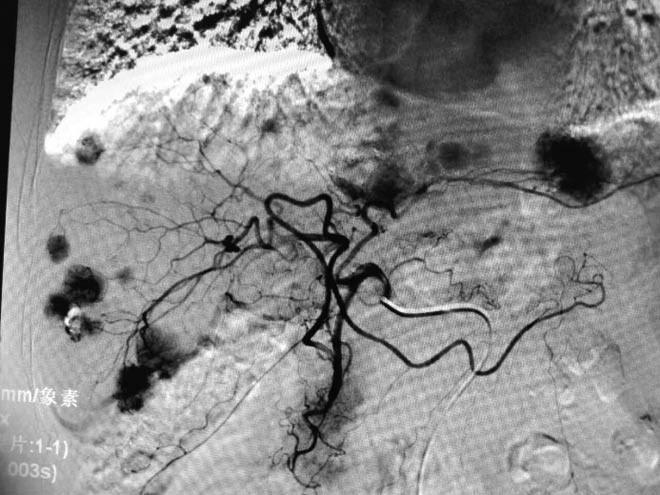

Thuốc nhuộm chỉ ra các khối đa ổ trong gan của bệnh nhân, trên phim chẩn đoán hình ảnh cho thấy từng khối thực thể tập trung tại các đầu mao mạch.

Hình ảnh cuối cùng cho thấy, không còn vị trí bắt màu nhuộm, thuốc đã hoàn toàn được đưa vào trung tâm của từng khối u, từng mao mạch cấp máu đều đã được nút mạch một cách chính xác.